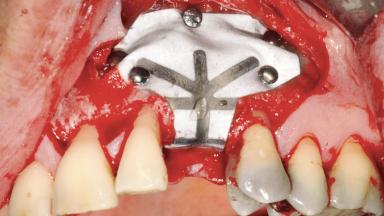

A 47-year-old Caucasian woman with a single-tooth edentulous space at the site of the left maxillary canine was referred for treatment. She had undergone traumatic extraction of this impacted canine several months before referral. Her chief complaint was the dissatisfying appearance of her smile. The patient desired a stable and esthetic rehabilitation of the site. Her dental history showed no evidence of periodontal disease or bruxism. She had no systemic diseases, was not taking any medications, and did not smoke. The extraoral examination revealed a high lip line and an inadequate soft-tissue volume at the defective canine site. Large black triangles were visible between the canine and its adjacent teeth.

Bone Augmentation Staged|Vertical

Augmentation Materials Autogenous chips|Membrane

Bone Volume Horizontally and vertically sufficient Horizontally deficient Deficient vertically or deficient vertically AND horizontally

Bone Volume Deficient vertically or deficient vertically AND horizontally